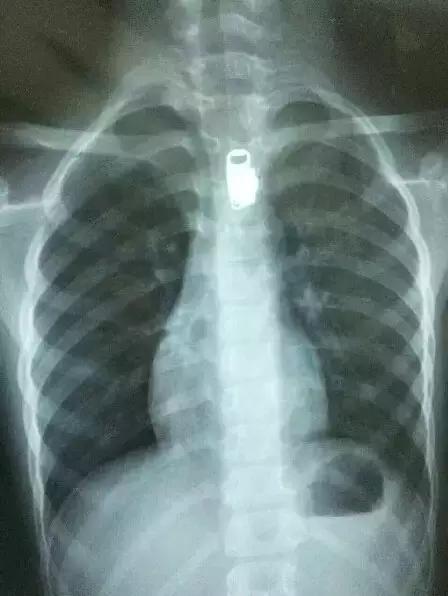

“我吞下去没什么感觉,可是刚才却疼了。”听了儿子的一席话,丁女士吓出一身冷汗。随即,她和丈夫商量后,立即带乐乐前往当地一所医院。经过胸部X光片,医生发现,乐乐的食管里确实有一个很像拉链头的异物,且异物清晰可见。

前天上午,家人带着乐乐赶往苏北医院。在苏北医院消化内科,医生朱振为患儿进行了检查。经过胃镜检查,朱医生发现,拉链头已到了孩子的食管中段,也就是食管第一个生理性的狭窄处。拉链头藏在男童食管里,距离孩子牙齿处约18厘米,胃镜显示已经造成了食管的损伤。

根据影像检查,医生发现拉链头卡在男童食管中段。

朱振告诉记者,若是拉链头不及时取出,会带来很严重的后果。拖的时间久了,会导致食管壁脓肿,甚至穿孔,很有可能进入胸腔的纵膈内,带来胸腔感染,到时只能做开胸手术了。